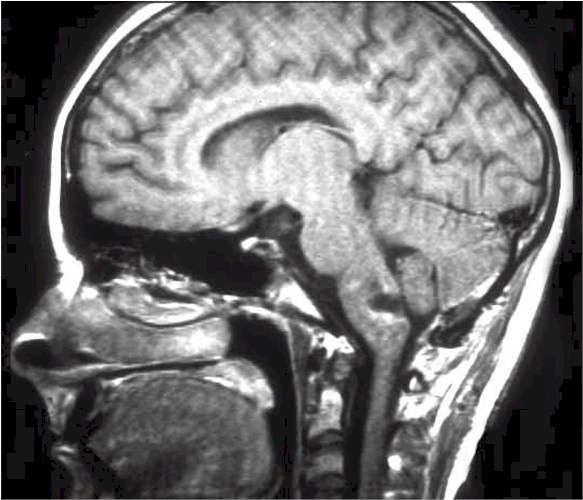

Esito postchirurgico. |

Sarà necessario un controllo neuroradiologico seriato per il rilievo precoce di un eventuale idrocefalo secondario che andrà opportunamente trattato chirurgicamente.